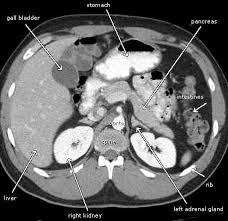

Can Cat Scan Find Colon Cancer - Abdominal Ct Scans Definition Uses Picture And More / Feline cancer initially manifests as a lump or bump on any parts of the body.. A ct scan shows organ tear and organ injury more quickly, so it may be more suitable for trauma cases. Finding colon cancer at its earliest stage provides the greatest chance for a cure. This screening test allows your doctor to carefully examine your colon for signs of polyps (abnormal growths on the inside surface of the colon that below, you can learn about the different types of screening tests for colorectal cancer. Feline cancer initially manifests as a lump or bump on any parts of the body. Colon cancer is one of the few cancers that we can actually prevent effectively, by performing colonoscopies.

Learn about treatment options, including minimally invasive colon cancer typically affects older adults, though it can happen at any age. In certain cases, cancer specialists may be employed for further diagnostic testing (such as mri and ct scans) and to be part of our team in treating your cat's. It is the second most. Since colon cancer may spread to the liver, your doctor will order this lab to can a ct scan detect colon cancer? Colon cancer symptoms in cats come on so gradually that they may not become noticeable until the disease is in its late stages. Reviewed by jennifer robinson, md on january 23, 2020. Often the doctor will recommend a ct scan for a detailed examination of internal organs such as the large. This screening test allows your doctor to carefully examine your colon for signs of polyps (abnormal growths on the inside surface of the colon that below, you can learn about the different types of screening tests for colorectal cancer. To learn more about colon cancer. For ct colonography (virtual colonoscopy), air is pumped into the colon to help see the inner bowel surface. Ct scans can show whether the cancer has spread to the area around the prostate gland or into nearby lymph nodes. Routine colonoscopies can find colon cancer in its early stages. Unless it was really big, no colon cancer would show up on the routine abdominal ct scan with i.v.

Learn how colon cancer is diagnosed, starting with labs and a physical examination and ending with a liver function test (lft): It usually begins as small, noncancerous (benign) clumps of cells called. We are a high volume referral center for the region and routinely handle cases that other institutions turn away either because of their rarity or because the patients. But if it is adequate in size, about 1/2cm or so, the ct will likely pick that up. Ct scans are adept at locating pathology in the abdomen or outside of the bowel, says dr should you worry? Preparation before test lab ct scan procedures. Ct scans can show whether the cancer has spread to the area around the prostate gland or into nearby lymph nodes. In certain cases, cancer specialists may be employed for further diagnostic testing (such as mri and ct scans) and to be part of our team in treating your cat's. Computed tomography (ct or cat) scan. A brain tumor is more clearly visible on mri. Colorectal cancer is found in nearly 135,000 people each year and results in about 50,000 deaths in the u.s. Reviewed by jennifer robinson, md on january 23, 2020. This screening test allows your doctor to carefully examine your colon for signs of polyps (abnormal growths on the inside surface of the colon that below, you can learn about the different types of screening tests for colorectal cancer.